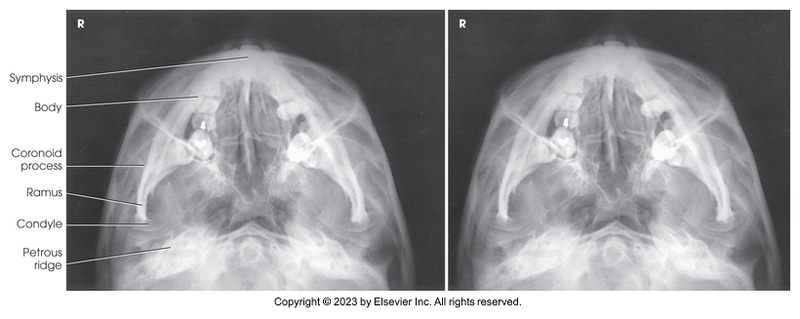

Submentovertical projection of mandible

Submentovertical of mandible